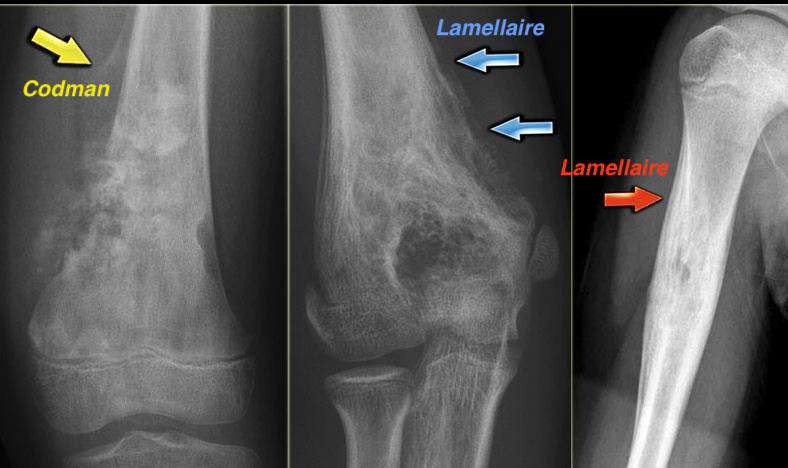

2. Réaction Périostée

- La réaction périostée touche tout ce qui irrite le périoste (malin, bénin, fracture(Cal osseux !), infection)

- La différence entre bénin et malin se fait sur le timing (l’os a le temps de se former correctement ou non)

- Bénin: compact, dense, en vague

- Malin: Triangle de Codman, Multi-couches / Lamellaire / Pelure d’oignon, Spiculé